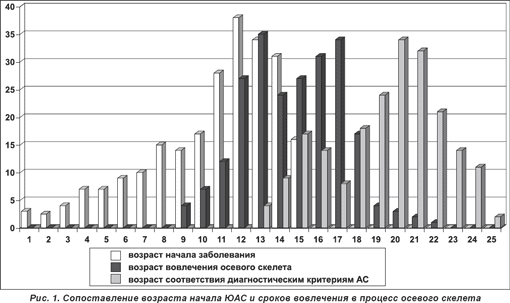

Важнейшей особенностью ЮАС, обусловливающей трудности ранней диагностики, является наличие «преспондилической» стадии, когда клиническая картина заболевания имеет неспецифические черты, малоотличимые от симптоматики других воспалительных заболеваний суставов у детей. Продолжительность этой преспондилической стадии до появления первых симптомов поражения позвоночника может составлять несколько (иногда более 10) лет и находится в обратной зависимости от возраста начала болезни (рис. 1). Эта закономерность течения ЮАС диктует необходимость тщательной оценки и интерпретации других клинических проявлений болезни для постановки диагноза либо прогнозирования развития ЮАС в дальнейшем.

Поражение осевого скелета почти у половины больных развивается в течение первого года, а у 20-30% — уже в дебюте ЮАС. Впервые симптомы вовлечения в процесс илеосакральных сочленений и позвоночника могут выявляться в возрасте 11-14 лет независимо от возраста начала ЮАС (см. рис. 1). Первым клиническим признаком осевого поражения обычно является боль в проекции сакроилеальных сочленений, проявляющаяся как активными жалобами, так и при физикальном обследовании. Важно подчеркнуть, что используемые для клинической диагностики сакроилеита у взрослых симптомы Кушелевского практически не имеют диагностической значимости для детей, вероятно, в силу высокой пластичности тканей в детском возрасте, что препятствует созданию перерастяжения в области крестцово-подвздошных сочленений, необходимого для выявления воспаления в этой области. Большей информативностью обладает оценка жалоб пациента, а также выявление пальпаторной болезненности в проекции сакроилеальных сочленений. Симптомы сакроилеита нередко уже с момента первого появления сочетаются с поражением поясничного и нижнегрудного или шейного отделов позвоночника. Характерные для взрослых интенсивные, преимущественно ночные, боли в спине нетипичны в детском возрасте и развиваются спустя значительный промежуток времени, давая основания для формального соответствия общепризнанным диагностическим критериям (Модифицированным Нью-Йоркским критериям) АС (см. рис. 1). Чаще всего у детей можно наблюдать непостоянные жалобы на чувство усталости и напряжения в мышцах спины с воспалительным ритмом, т.е. возникающие в ранние утренние часы и уменьшающиеся после физических упражнений. Иногда выявляются локальная болезненность, ограничение объема движений, сглаженность физиологических изгибов позвоночника, особенно поясничного лордоза, региональная гипотрофия мышц (рис. 2). У части больных эти симптомы значительно уменьшаются или полностью исчезают после адекватного лечения, а повторные рецидивы могут возникнуть лишь через несколько лет.